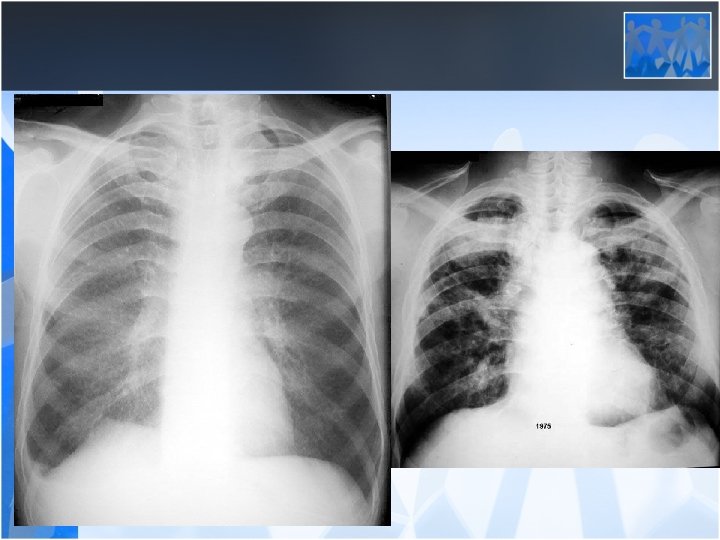

• Acute Silicosis (Silicoproteinosis, alveoloproteinosis) – Exposure to high concentrations of cristaloid silica, symptoms occur in a few months time – Cough, weight loss, fatique – Diffuse crackles – Lower zone asiner infiltrations on chest x ray – Progression to fulminan respiratory failure over several months – Survival after the onset of symptoms<2 years

• Chronic Silicosis – Initial exposure to the onset of the disease is >15 years – No symptoms in the beginning – Dispnea and nonproductive cough is the main symptoms and when it is syptomatic it is usually in the form of PMF(PMF: Progressive massive fibrosis)

• Radiology is the most important diagnostic method for silicosis • Mainly upper and middle zone 3 -10 mm noduler opacities (silicotic nodules) • ILO clasification p, q, r • Hiler calcification (Egg shell calcification) PMF: • Coalescence of radiologic opacities (conglomeration • Nodules>10 mm • ILO clasification A, B, C • Honey combing can be seen in end stage disease